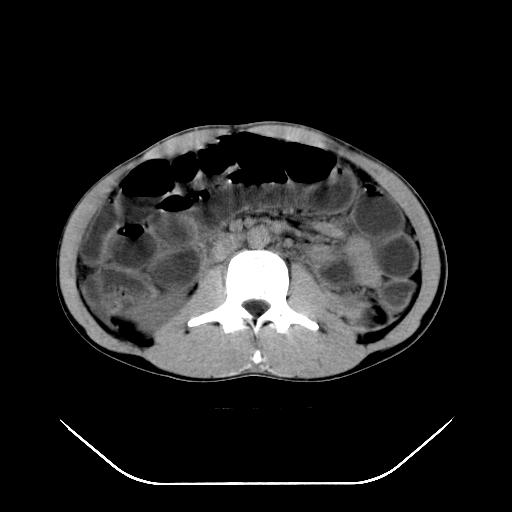

m-25y 高空堕落 12 月5号

12月7号病人尿量200ml/24h 急查双肾ct

左肾挫裂伤并肾周血肿;

支持:1、左肾挫裂伤并肾周血肿;

2、少量腹水;

3、左肾旋转不良;

4、反射性肠淤张。

反射性肠郁张是指许多原因造成肠道吸收气体和液 功能障碍,也可造成分泌功能与动力的障碍,以致肠道内有过量的气体和液体潴积,有时只有过量的气体潴积。肠道较舒张,但不扩大,或有部分肠道轻度的扩大,这种情况叫做反射性肠郁张 ,这个病人的肠管扩张太明显了。

提示有肠梗阻的可能性?

我不同意守望可西里老师所说的有输尿管的血液凝积一说,首先从这个图像来看输尿管的走行太偏外了,输尿管是肾盂向下延续的部分,开始在腰大肌的外缘,逐渐向内偏移,接近或越过腰椎横突的外端。而守望可可西里老师所指的这段图像位置太靠外了,且总是伴行在一段肠管的前缘。第二,如果有血液的凝积,可造成肾盂肾盏的扩张积水,而这个病人的肾盂肾盏的形态一直很好。

综上所述,考虑1:左肾挫伤并包膜下血肿2:少量腹腔积液3:肠梗阻的可能

除了1:左肾挫裂伤并肾周血肿;

2:少量腹水

第二次ct检查后:临床医生腹水穿刺后考虑肠系膜动脉破裂,后实行剖腹探查:于空肠距离十二指肠90cm处发现肠管破裂,破裂口较小;修补后关腹。